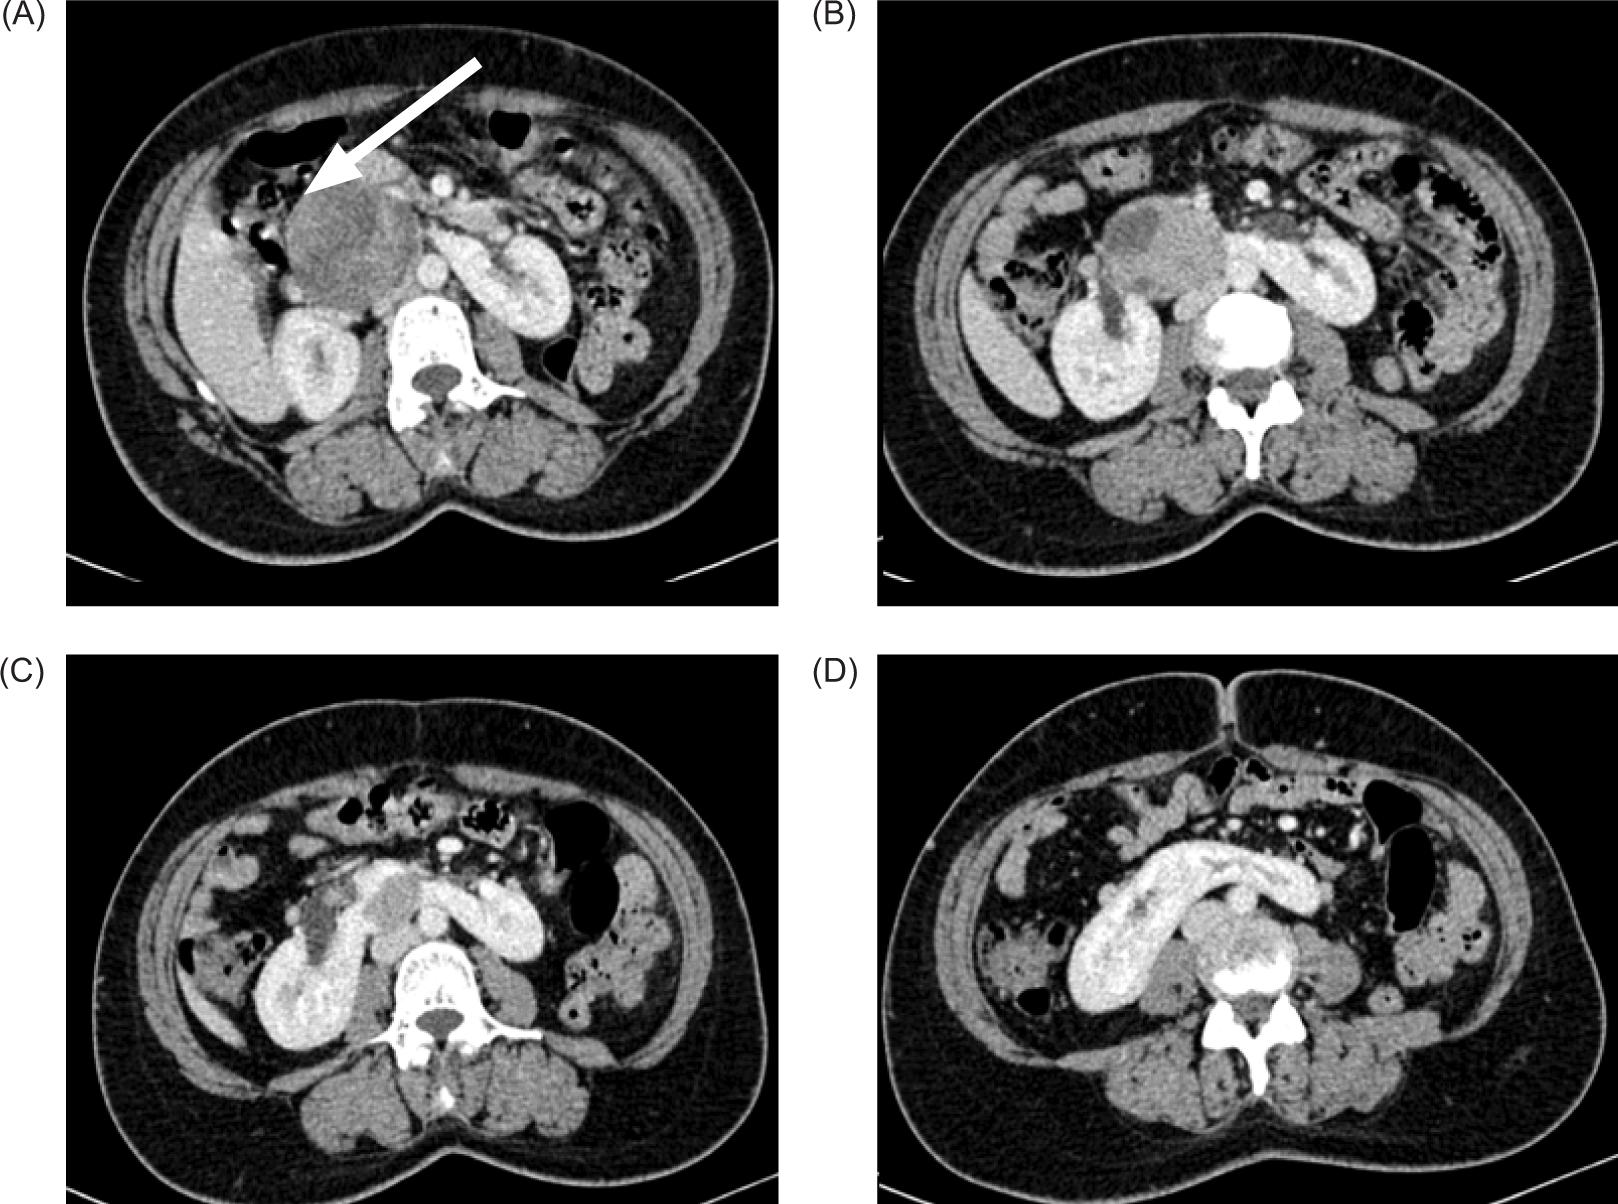

Plain and contrast-enhanced CT scan of abdomen was performed for further evaluation. It revealed HSKs with lower pole of both kidneys deviated medially and fused in midline with renal parenchyma measuring 2.1 cm in thickness and 3.3 cm in cranio-caudal extent. Calyces of lower pole of both kidneys were directed medially. Left kidney showed a bifid renal pelvis. A large, well-defined solid mass of heterogeneous density showing heterogeneous post-contrast enhancement measuring 66 x 54 x 57 mm (transverse x anteroposterior x craniocaudal, respectively) was noted arising from the superior portion of isthmus and extending superiorly at adjoining retroperitoneum and abutting medial surface of right kidney up to renal hilum with obscuration of intervening fat plane. It was extending anterior to right renal hilum and abutting anterosuperior surface of right renal pelvis (Figure 2).

Figure 2: Contrast-enhanced CT coronal sections showing medially deviated lower poles of the bilateral kidneys with heterogenous enhancing mass arising from the superior portion of isthmus of the HSK abutting the hilum of right kidney.

This mass was causing extrinsic compression and anterior displacement of distal portion of second part and proximal portion of third part of duodenum that were compressed and displaced anteriorly (Figure 3).

Figure 3: (A–D) Axial contrast enhanced CT abdomen showing well-defined heterogeneously enhancing solid mass arising from isthmus compressing and displacing adjoining second and proximal third portion of the duodenum (arrow in [A]).

The pancreatic head was compressed and displaced anteriorly; posteriorly mass effect was noted on anterior surface of inferior vena cava with obliteration of intervening fat plane. IVC as a result was compressed and flattened anteroposteriorly (Figure 4).